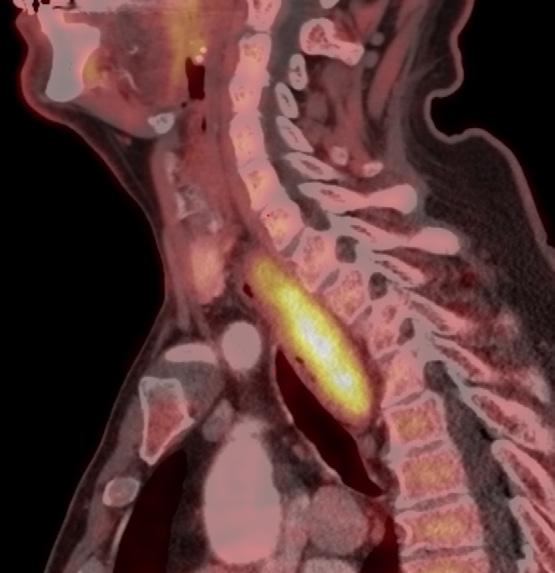

BILDE 1: Initial CT collum viste tumorstørrelse på 70x54 mm. CT undersøkelse en måned senere som var tre dager etter fullført strålebehandling viste tumor-reduksjon til 55x48mm. CT undersøkelse etter ytterligere tre måneder med tillegg av dabrafenib og trametinib viste at tumor hadde gått tilbake til tre cm i størrelse. Samtykke til publisering av røntgenbildene er innhentet fra pasientens ektemann da pasienten er død.

KASUISTIKK 1

En 72 år gammel kvinne oppsøkte fastlegen med nyoppstått 2x2 cm stor kul på halsen. Hun ble henvist til ultralydundersøkelse lokalt og senere ble det utført finnålsprøve samme sted, som ga mistanke om anaplastisk karsinom. Da hadde svulsten vokst til 8 cm. Hun ble henvist til regionsykehus og innlagt neste dag. Grovnålsbiopsier bekreftet anaplastisk thyreoideakarsinom. Pasienten hadde da utviklet heshet og smerter, men hadde ikke svelgvansker eller dyspné. Tumor i thyroidea var inoperabel, samt at hun hadde multiple små lungemetastaser. Det ble startet med strålebehandling to ganger daglig (1,5 GYx30-45) samt ukedose doksorubicin. Behandlingsrespons ble evaluert med CT-undersøkelse (Bilde 1). Det ble påvist BRAF (V600E) mutasjon, og etter fullført strålebehandling ble det startet med BRAF-/MEK hemmerne dabrafenib 75 mg x 1 og trametinib 1 mg x 1 en måned etter innleggelsen. Dosen ble økt etter ni dager. Tumor og metastaser på hals og i lunger viste komplett respons, og pasienten ble operert med venstresidig hemithyreoidektomi etter fem måneder. Det var betydelige adheranser og forandringer rundt thyroidea relatert til tidligere behandling. Endelig histologi viste kun enkeltliggende tumorceller i thyreoidealappen. Dabrafenib 100 mg x 2 og trametinib 2 mg x1 ble kontinuert med enkelte pauser på en til tre uker på grunn av nøytropen feber.